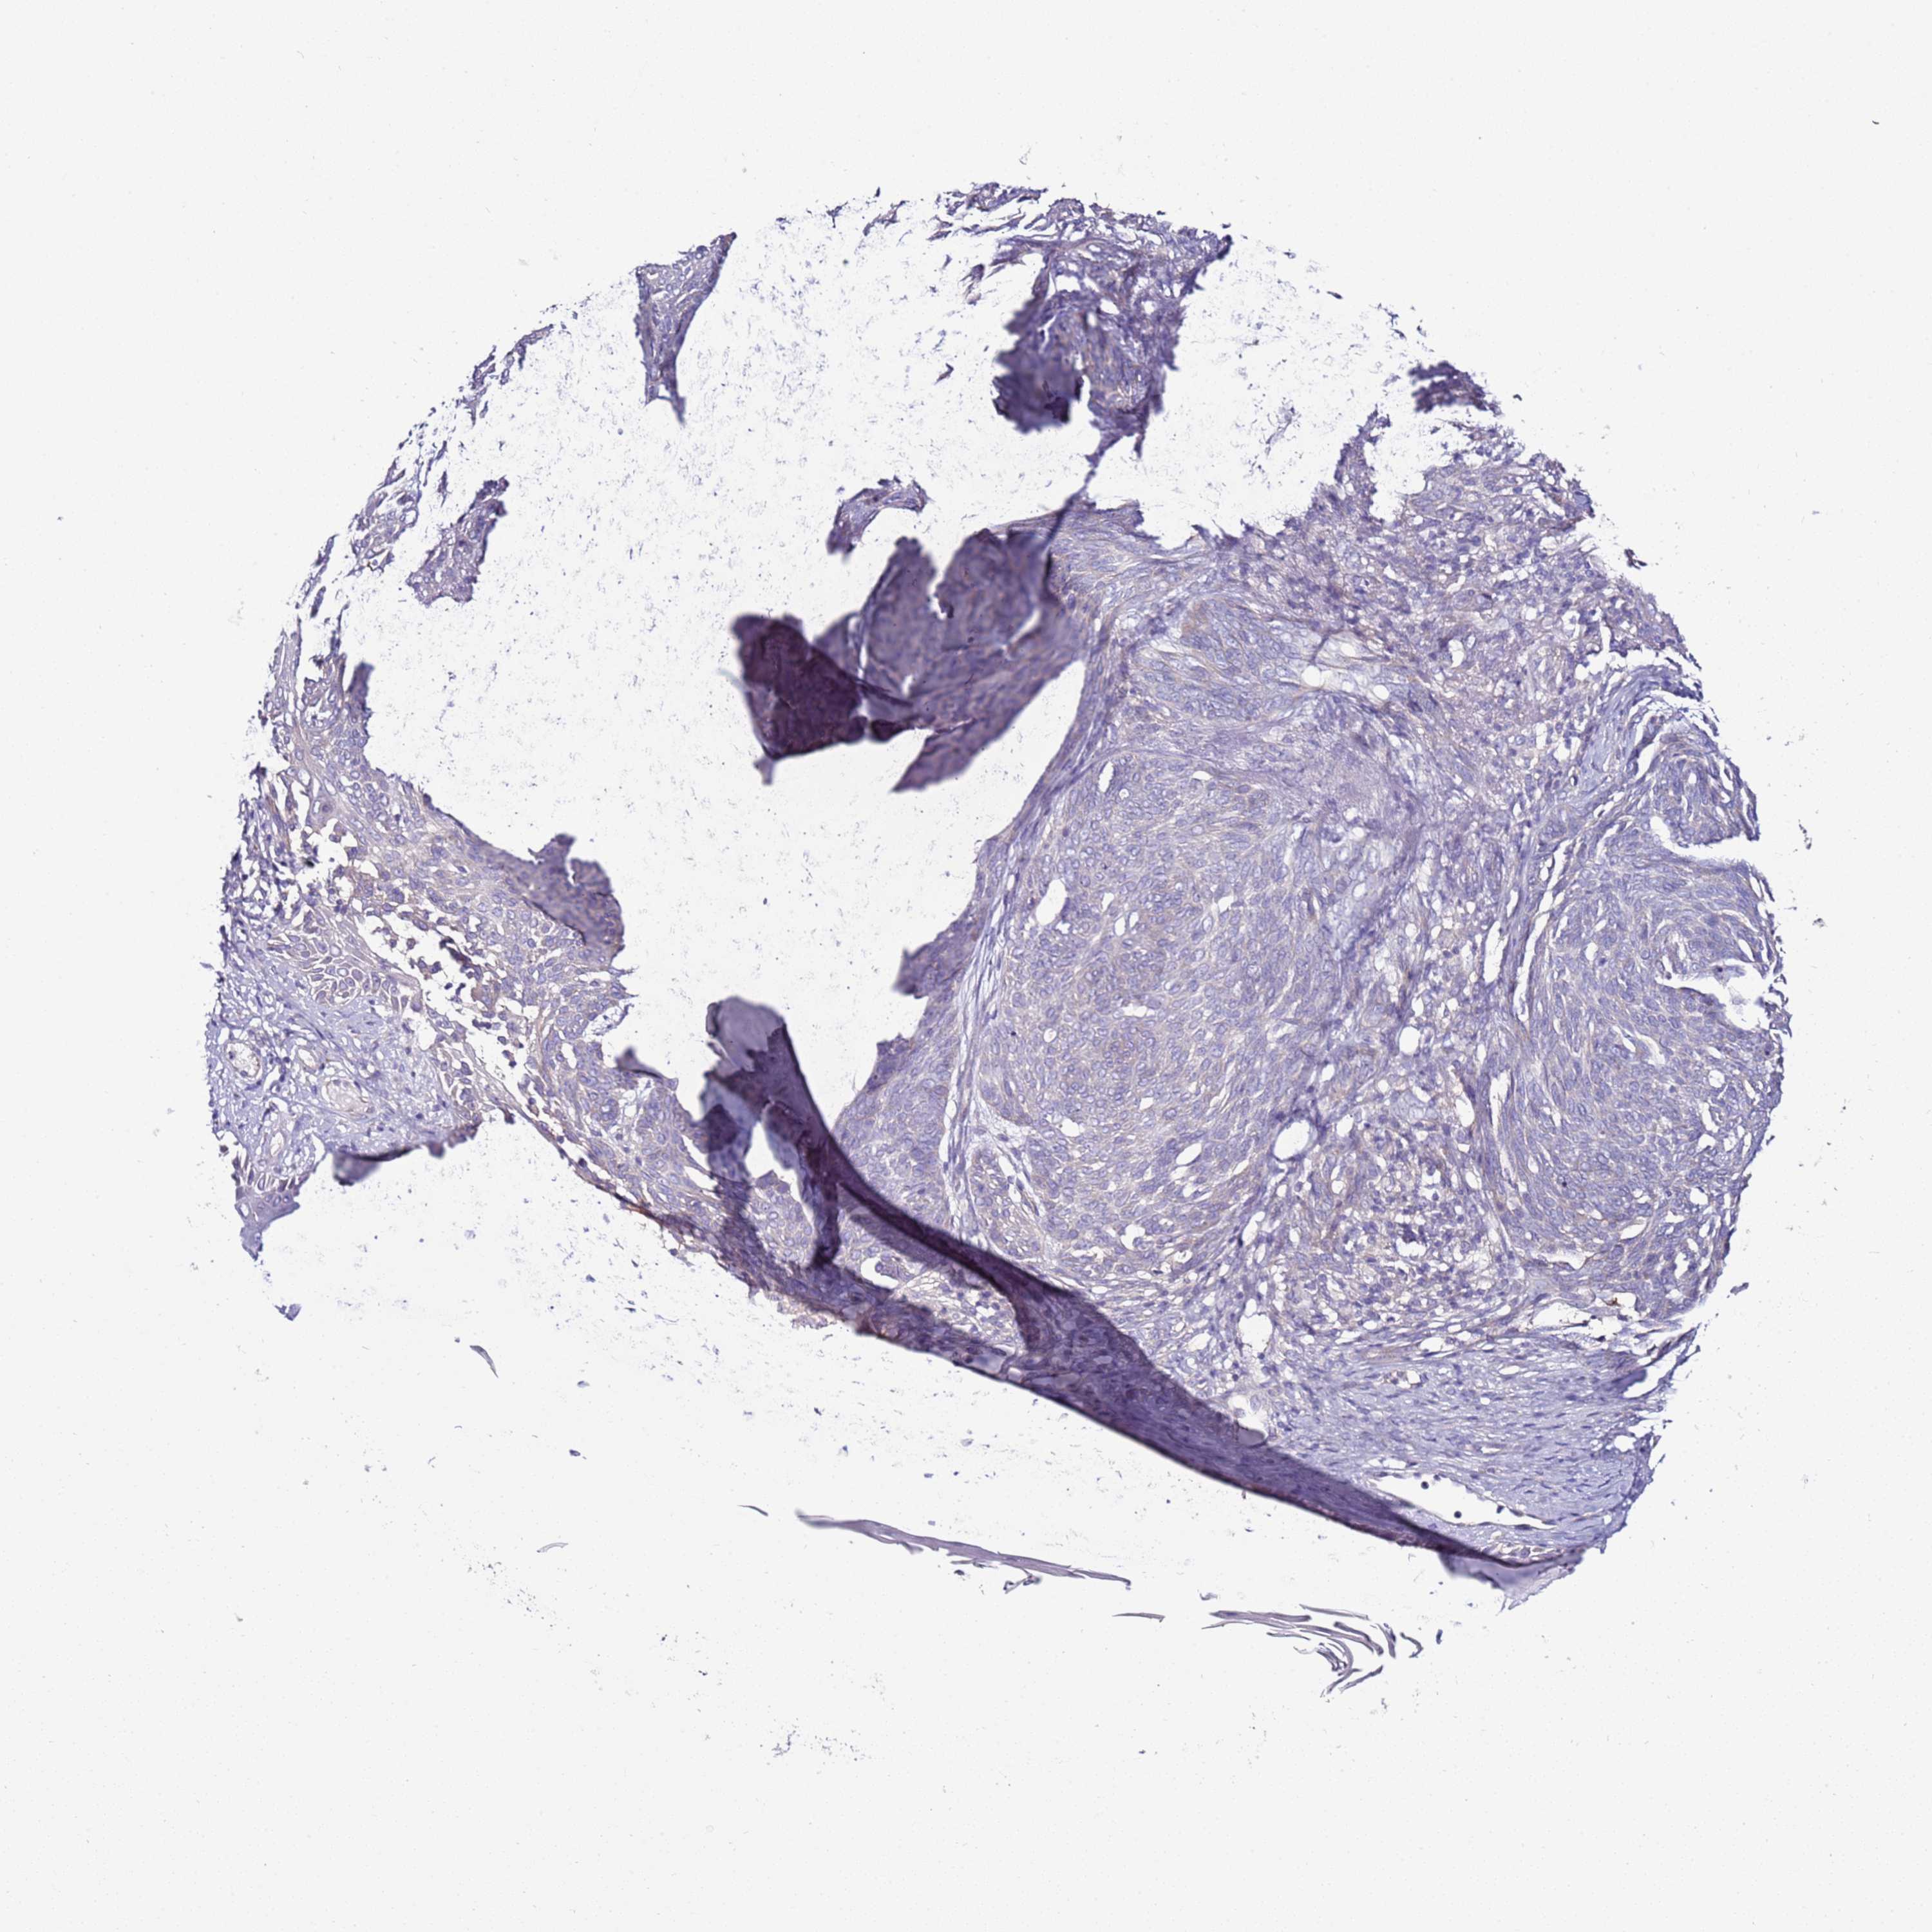

SKIN CANCER - Protein expressioni

A mouse-over function shows sample information and annotation data. Click on an image to view it in a full screen mode. Samples can be filtered based on level of antibody staining by selecting one or several of the following categories: high, medium, low and not detected. The assay and annotation is described here.

Each image is clickable and will lead to virtual microscopy that enables deeper exploration of all samples and also displays staining intensity scores, fraction scores and subcellular localization as well as patient and tissue information for each sample.

Antibody HPA039764

Basal cell carcinoma

Squamous cell carcinoma, NOS

Squamous cell carcinoma, metastatic, NOS

Squamous cell carcinoma in situ, NOS